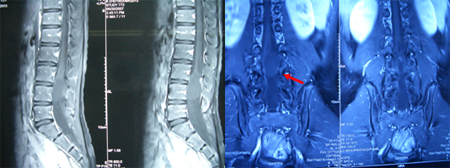

术中发现脊髓圆锥末端囊性占位病变,大小约3×2.5cm2,其背侧有一1cm2大小的硬性肿物,有神经根粘连,镜下分离神经,切除硬性肿物,囊内容为胶水样透明粘液。如下图所示: